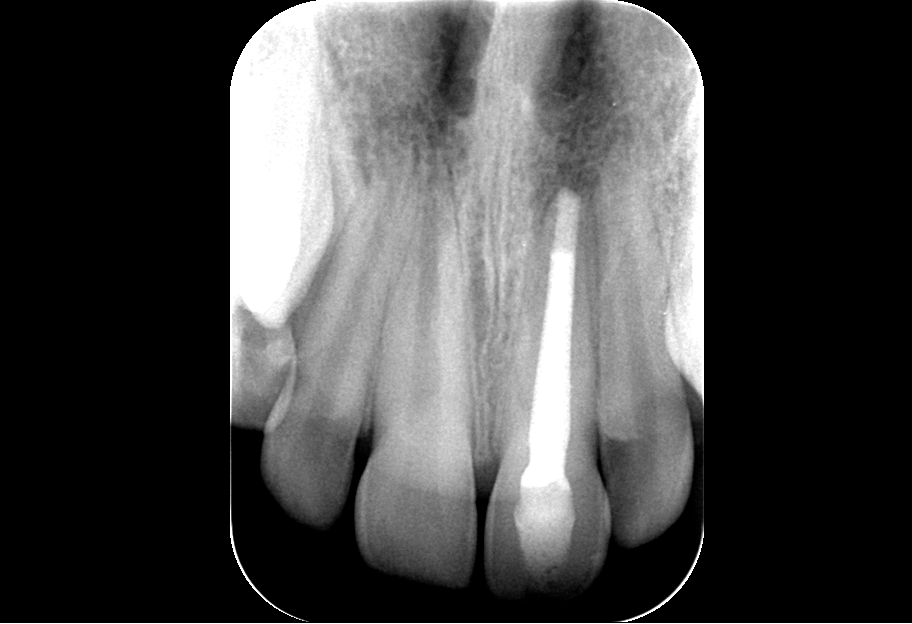

Im jungen bleibenden Gebiss stellt der noch mehr oder minder offene Apex spezielle Anforderungen, bietet aber auch Chancen bei der Behandlung. Das Behandlungsspektrum reicht hier von einer partiellen Kariesexkavation, direkter Überkappung, Pulpaamputation, konventioneller Wurzelfüllung über apikalen Plug bis hin zur Revitalisierung. Die verschiedenen Methoden, ihre Indikationen und Grenzen werden vorgestellt.